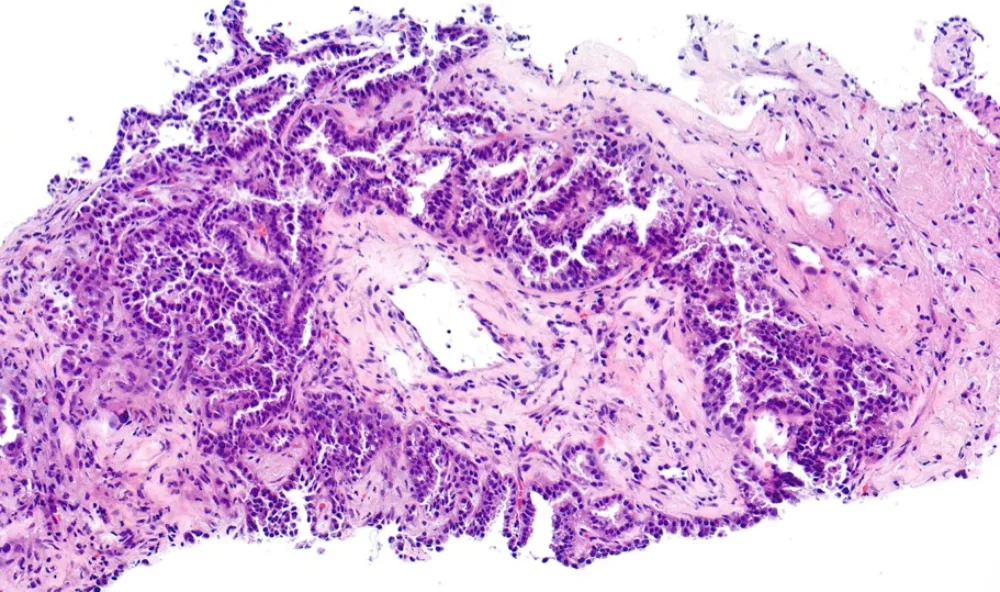

6-HE 2. Biopsia pulmonar

Diagnóstico: ADENOCARCINOMA PULMONAR INFILTRANTE DE PATRÓN PAPILAR Y MICROPAPILAR. ESTUDIO NGS: MUTACIÓN L747_S752 EN EL GEN EGFR

- El patrón micropapilar del adenocarcinoma se asocia a un mayor grado histológico, mayor invasión linfovascular y peor pronóstico. (PMID: 18516041)

- El adenocarcinoma de patrón micropapilar presenta más alteraciones en el gen EGFR, después del adenocarcinoma lepídico y acinar. (PMID: 31692283)